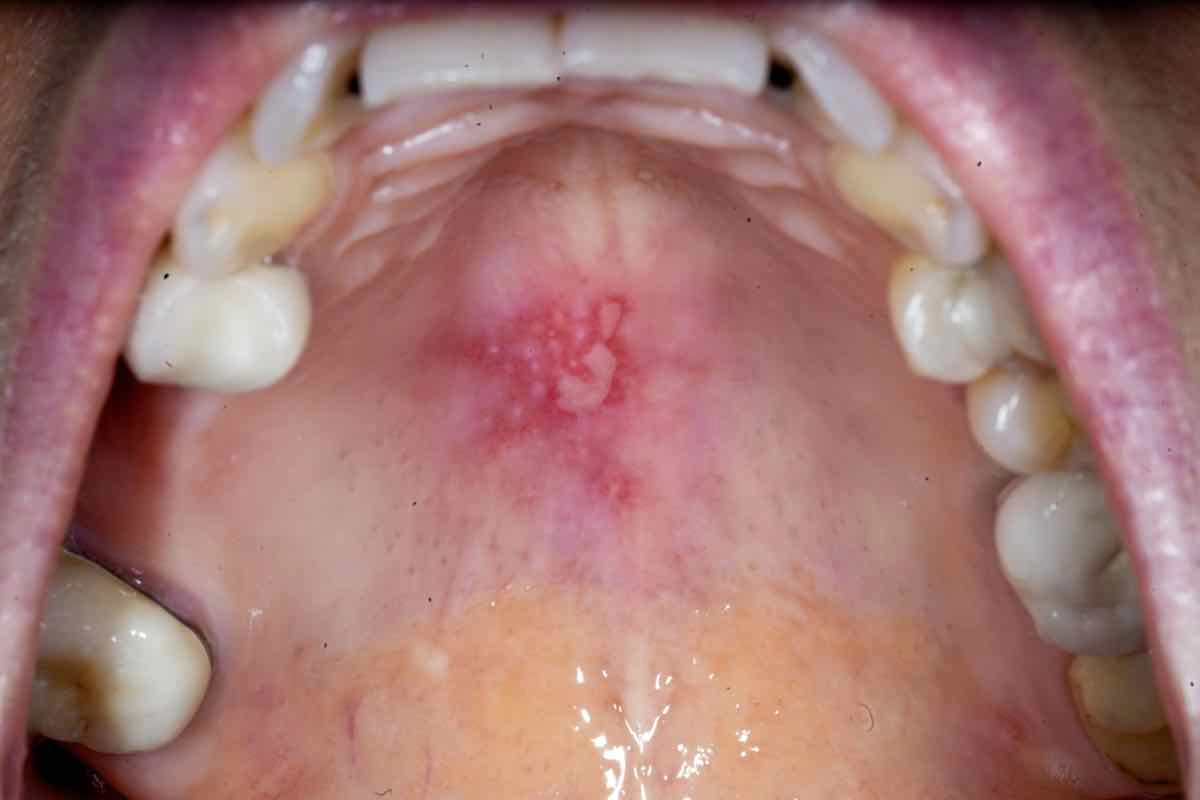

Orale blemmer er vanligvis lett å identifisere på grunn av deres karakteristiske utseende. De vises som små, smertefulle blemmer eller sår fylt med væske, ofte på innsiden av kinnene, tungen, leppene eller i ganen. De kan også være hvite, røde eller gule i fargen og omgitt av rød og hoven hud.

Væske fylte blemmer i munnen er en vanlig, men ubehaglig tilstand som kan påvirke både voksne og barn. De kan variere i størrelse og farge og dukke opp hvor som helst i munnen, på leppene eller på tungen. De kan oppstå av mange årsaker og er vanligvis smertefull. Ofte er de forårsaket av virusinfeksjoner, irritasjon fra skarpe tenner eller tannproteser. Blemmene behandles vanligvis med en kombinasjon av smertelindring og god munnhygiene.

Blemmer i munnhulen er små, smertefulle sår eller lesjoner som oppstår på slimhinnen i munnen. De kan variere i størrelse og form og kan være hvite, røde eller gjennomsiktige. -

Blemmer i munnhulen kan klassifiseres i ulike typer, inkludert aftøse sår, herpeslesjoner, blemmer forårsaket av tannproteser og blemmer assosiert med autoimmun sykdom som lichen planus. Disse blemmene kan variere i utseende, årsak og behandling. -